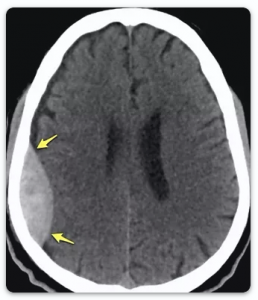

Epidural Hematom (Kanama): Beyni saran zar (dura) ile kafatası kemiği arasında olan, beyin ile direkt ilgisi olmayan kanamalardır. Ancak kanamanın devam etmesi ve boyutlarının artması halinde beyni sıkıştırarak hasar verebilirler. Tüm kafa travmalarının %1’inden azını oluştururlar. Sıklıkla kırık kemik kenarlarının, dura üzerindeki damarları kesmesi sonucu oluşur. Bazen kırık kemik kenarlarından olan kanama sonucu da oluşur. Nadiren de olsa beynin ana toplar damarlarından da kaynaklanabilir. Şayet erken olarak tedavi edilebilirse sonuçları çok iyidir. Çünkü beyin üzerinde yarattıkları hasar sınırlıdır. Ameliyat sonrası sonuçlar, hastaların ameliyata girmeden önceki nörolojik tabloları (Glaskow Koma Skorları) ile bağlantılıdır. Yani bilinç durumu kötü halde ameliyata giren hastalarda ameliyat sonrası da sakatlık kalma ihtimali daha yüksektir. Kimi hastalarda kanama boyutları ameliyat gerektirecek boyutlarda olmayıp, hastanede sıkı gözlem altında takip edilirler. Kimi hastalar ise acil olarak ameliyat gerektirirler. Ameliyatta kanamanın olduğu bölgedeki kafatası kemiği kaldırılır, kanama temizlenir ve kanamanın kaynağı durdurulur. Son olarak kaldırılan kemik tekrar eski yerine sabitlenerek ameliyat tamamlanır.